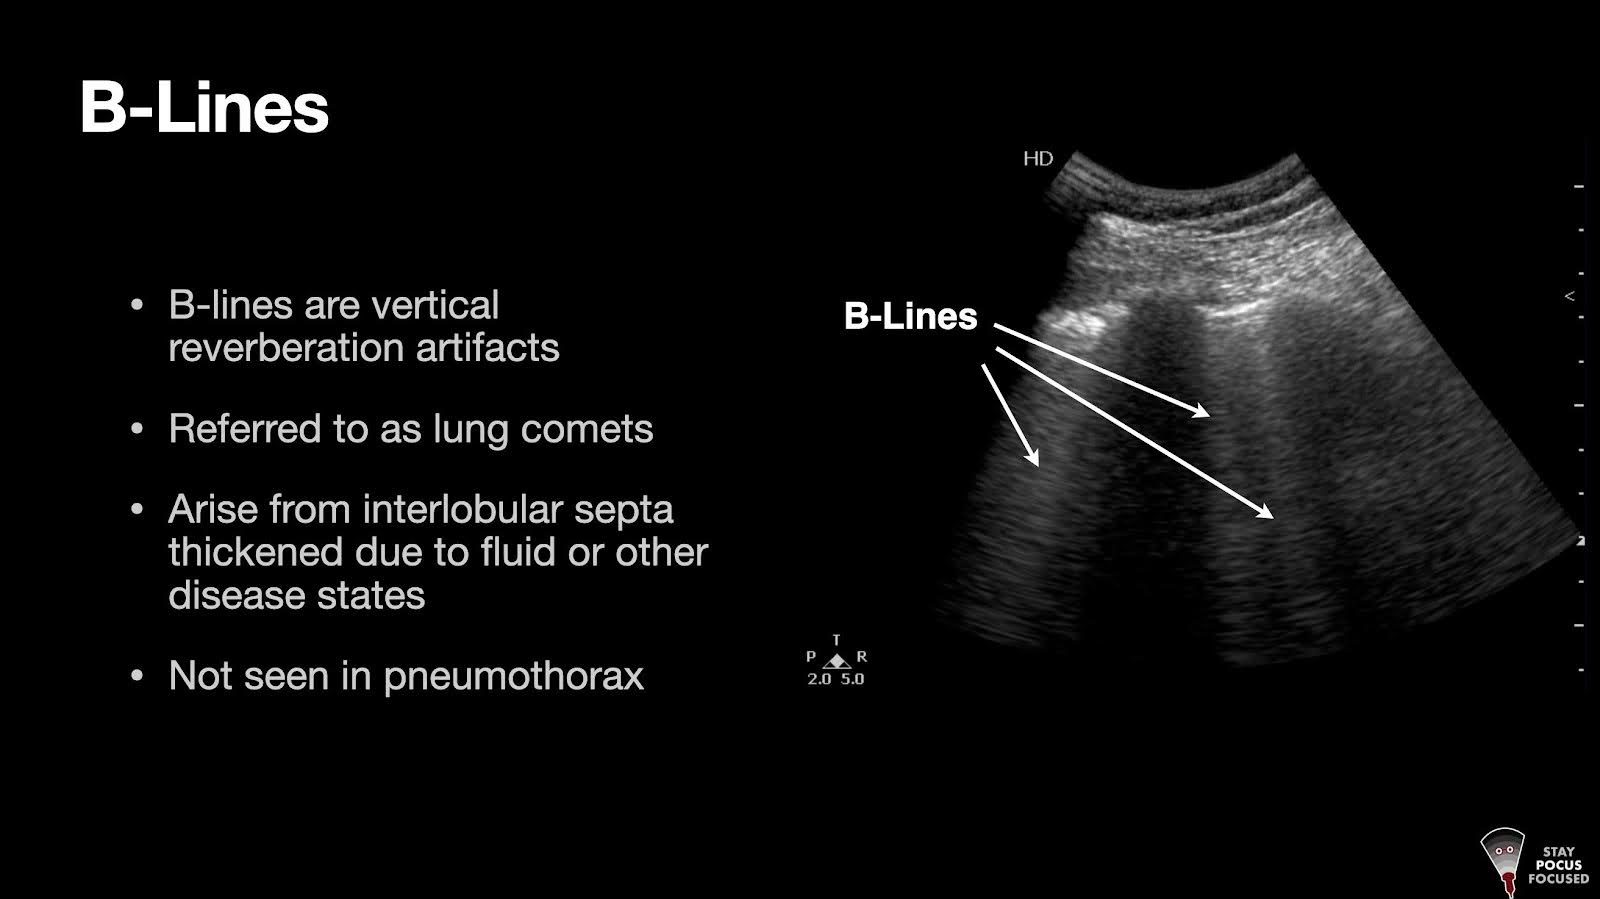

• B-lines

• Plethoric IVC

• Reduced LV without RV strain